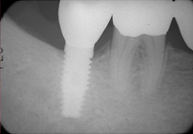

그림에서 보는 것처럼 턱뼈 안에 치아의 뿌리에 해당하는 매식체(티이타늄이라는 금속으로 되어있습니다)를 심고 그 위에 치아의 머리부분에 해당하는 보철물을 장착하는 시술법입니다.

(1차수술)1차수술은 국소마취하에 시술되는데, 우리는 사랑니를 뽑을 때 하는 마취와 같습니다. 수술은 인공치아를 몸속뼈 속에 심는 과정입니다. 수술후 1~2주후 실밥을 풀게 되며, 이후 임플란트와 잇몸뼈가 엉겨붙게 되는 과정 즉, ‘골유착’이 일어나기를 기다리게 됩니다.

(2차수술 및 보철)2차 수술 또한 국소마취하에 시행합니다. 2차수술은 1차수술때 심은 임플란트에 기둥(지대주)를 연결하는 과정입니다. 2차수술 후 잇몸이 아무는 1~2주 후 치아머리 부분의 보철물을 제작하게 됩니다.